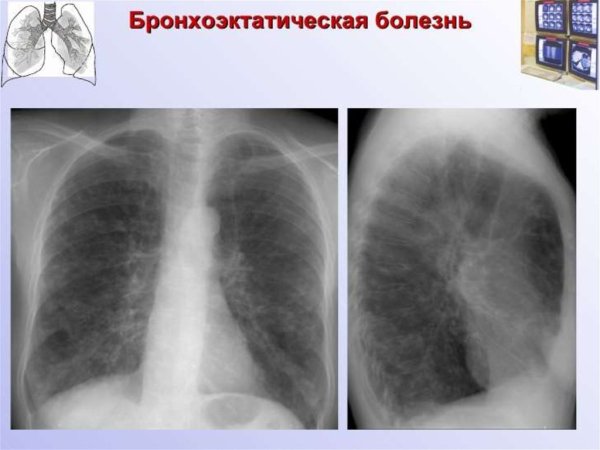

Деформация легочного рисунка - это состояние, при котором образование и распределение сосудистых и бронхиальных структур в легких претерпевает изменения. Это может быть следствием различных заболеваний, например, хронической обструктивной болезни легких (ХОБЛ), бронхоэктазов, фиброза легких или эмфиземы. Как результат, легочный рисунок становится нарушенным, что приводит к ограничению функции дыхания и возможному ухудшению общего состояния пациента. Для диагностики и оценки деформации легочного рисунка используются различные методы, такие как рентгенография грудной клетки, компьютерная томография или магнитно-резонансная томография. Лечение деформации легочного рисунка зависит от основного заболевания и может включать фармакотерапию, физиотерапию или хирургическое вмешательство.